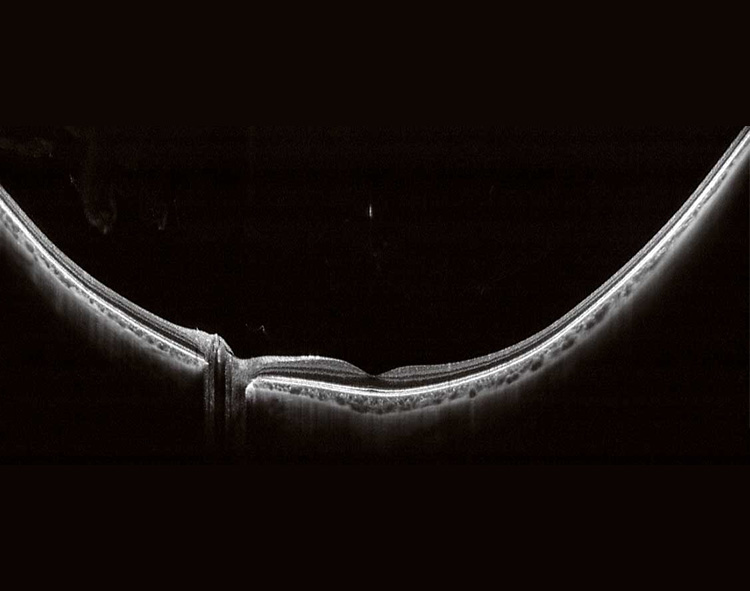

Глибина сканування з технологією частотно-модульованого джерела від Canon дозволяє краще проникнення при катаракті, крововиливах та через кровоносні судини та склеру й з легкістю чітко візуалізувати глибокі шари ока – сітківку та хоріоідею за одне сканування. Ще одна перевага Xephilio OCT-S1 - це можливість чітко відтворити зображення скловидного тіла та судинної оболонки (хоріоідеї) в одне сканування, без необхідності витрачати час на сканування скловидного тіла та хоріоідеї окремо.

Частотно-модульоване джерело Xephilio OCT-S1 дозволяє отримати широкопольне ОКТ зображення 23 x 20 мм, що може бути дуже корисним для спостереження за товщиною сітківкі при відшаруванні сітківки або пігментного ретиніту. Мозаїчне зображення дозволить створити неймовірне широкопольне ОКТ зображення 31 x 27 мм.